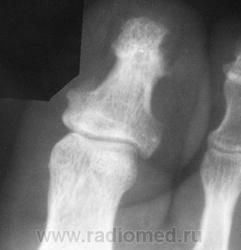

Пациент 1969 г.р. пришел к травматологу с жалобами на боли в I пальце. Палец гиперемираван, отечен. Болеет несколько дней.  Травму как таковую отрицает, хотя недавно был легкий ушиб этой области. Не могу понять что это. На остеомиелит, по-моему, не похоже, хотя... Травматический характер изменений сомнительный. Что-нибудь опухолеподобное в мягких тканях? Проследить пациента скорее всего не удастся. Хотелось бы услышать мнение коллег.

На недавние изменения не похоже.Похоже на следствие хронической компрессии (склеротический ободок), действительно, как при мягкотканных образованиях (например, узелки Бушара и Гебердена)).

Гломусная опухоль ногтевого ложе I п.

Поясните, что это. Наши хирурги такого не ставят. Скиалогически: краевой дефект костной ткани ногтевой бугристости дист.фаланги 1 пальца, со склерозированным и местами нечетким волнистым контуром. Может фиброма. Резкого пороза, как при панариции, не видно. На тофус не похоже, тем более не сустав. Узлы Гебердена и Бушара - метаболическая артропатия, к ногтевой бугрстости отношения не имеют. Акроостеолиз при склеродермии и т.п. выглядит иначе.

Против остеолиза - изолированное одиночное поражение одного пальца

Попросите УЗИ стов провести датчиком. По мне, так хондрома.

Гломус (Glomus, Множ. Glomera) - соединение между небольшой артерией и веной, проходящее в коже конечностей. Основной функцией гломуса является регуляция температуры в организме. Иногда нарушение развития гломуса или его чрезмерное разрастание приводят к образованию безвредной, но нередко крайне болезненной опухоли (опухоли гломуса (glomus tumour), или гломангиомы (glomangioma)); обычно эта опухоль развивается в коже на концах пальцев рук и ног. Она может быть каутеризована или удалена хирургическим путем. (Гломусы - мелкие округлые тельца диаметром 2-3 мм, состоящие из гломусных клеток, свободных нервных окончаний вегетативных нейронов. В каротидном, аортальном, легочном гломусах залегают хеморецепторы)

Энхондрома скорее, конечно).

Спасибо Леониду! Почитала про гломусные опухоли. Получается, такой диагноз ставится клинически (проба со жгутом), и каких-то особых показаний для лучевых методов диагностики нет. Краевая костная узурация контактно может иметь место. Но гломус обычно на тыльной, реже на ладонной поверхности, и такой дефект, как на представленном автором снимке, мало вероятен при гломусной опухоли. Хотя... если Леонид представит свои наблюдения, будет просто замечательно и поучительно!

В памяти 1 случай. У женщины был с чёткими контурами дефект бугристости ногтевой фаланги 2 пальца.

Палец не давала трогать из-за резкой боли, возникающей при пальпации.

Может, эпидермоидная киста или просто инфицированный вросший ноготь? При вросших ногтях ногтевые фаланги бывают такими деформированными.